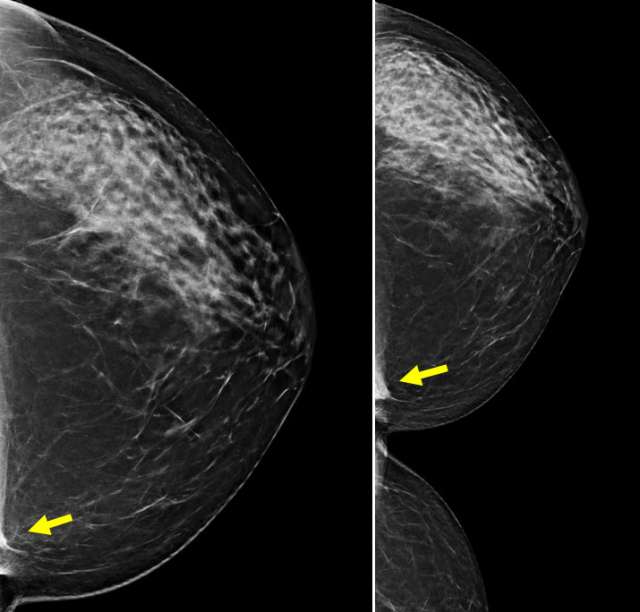

Mammographic Appearance

On mammography, the sternalis muscle presents as a variably shaped fibroglandular asymmetry on craniocaudal (CC) views, located in medial hemisphere at posterior depth (3). Sternalis muscles are not usually seen on mediolateral (ML) or mediolateral oblique (MLO) views. If the accessory muscle is incompletely visualized on the initial CC view, a cleavage view may be helpful to achieve better visualization. The appearance can mimic that of a skin lesion, lymph node, or other breast mass, potentially leading to misinterpretation.